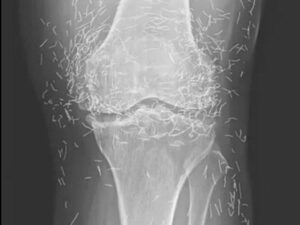

Years later, when doctors took X-rays to evaluate her knee condition, they weren’t prepared for what appeared on the images. Her knees were filled with dozens of bright, metallic flecks — tiny needles embedded deep within the joint area.

The findings were later documented in a case published by the New England Journal of Medicine.